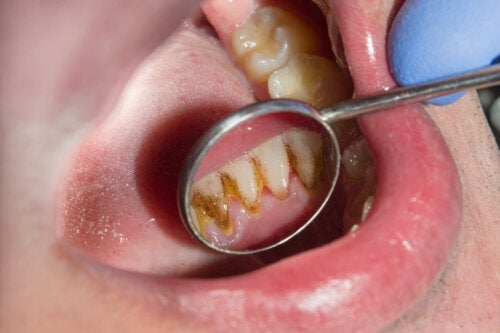

Цветът на зъбния камък зависи до голяма степен от това колко е стар и къде се намира. Най-честите области, където бактериалната плака започва да се втвърдява, са тези в близост до каналите, през които слюнката излиза от устата. Това е от вътрешната страна на долните резци и от външната повърхност на моларите.

Когато е едва оформен и е над линията на венците, зъбният камък е по-светъл. В тези случаи се нарича супрагингивален зъбен камък и има жълт или светлокафяв цвят.

Когато зъбният камък е по-стар и се е натрупал, обичайно е той да започне да се отлага под венеца. Това е известно като субгингивален зъбен камък.

Субгингивалният зъбен камък и отлаганията, които са били дълго време в устата, потъмняват. По този начин те могат да изглеждат кафяви, черни или зелени на цвят.